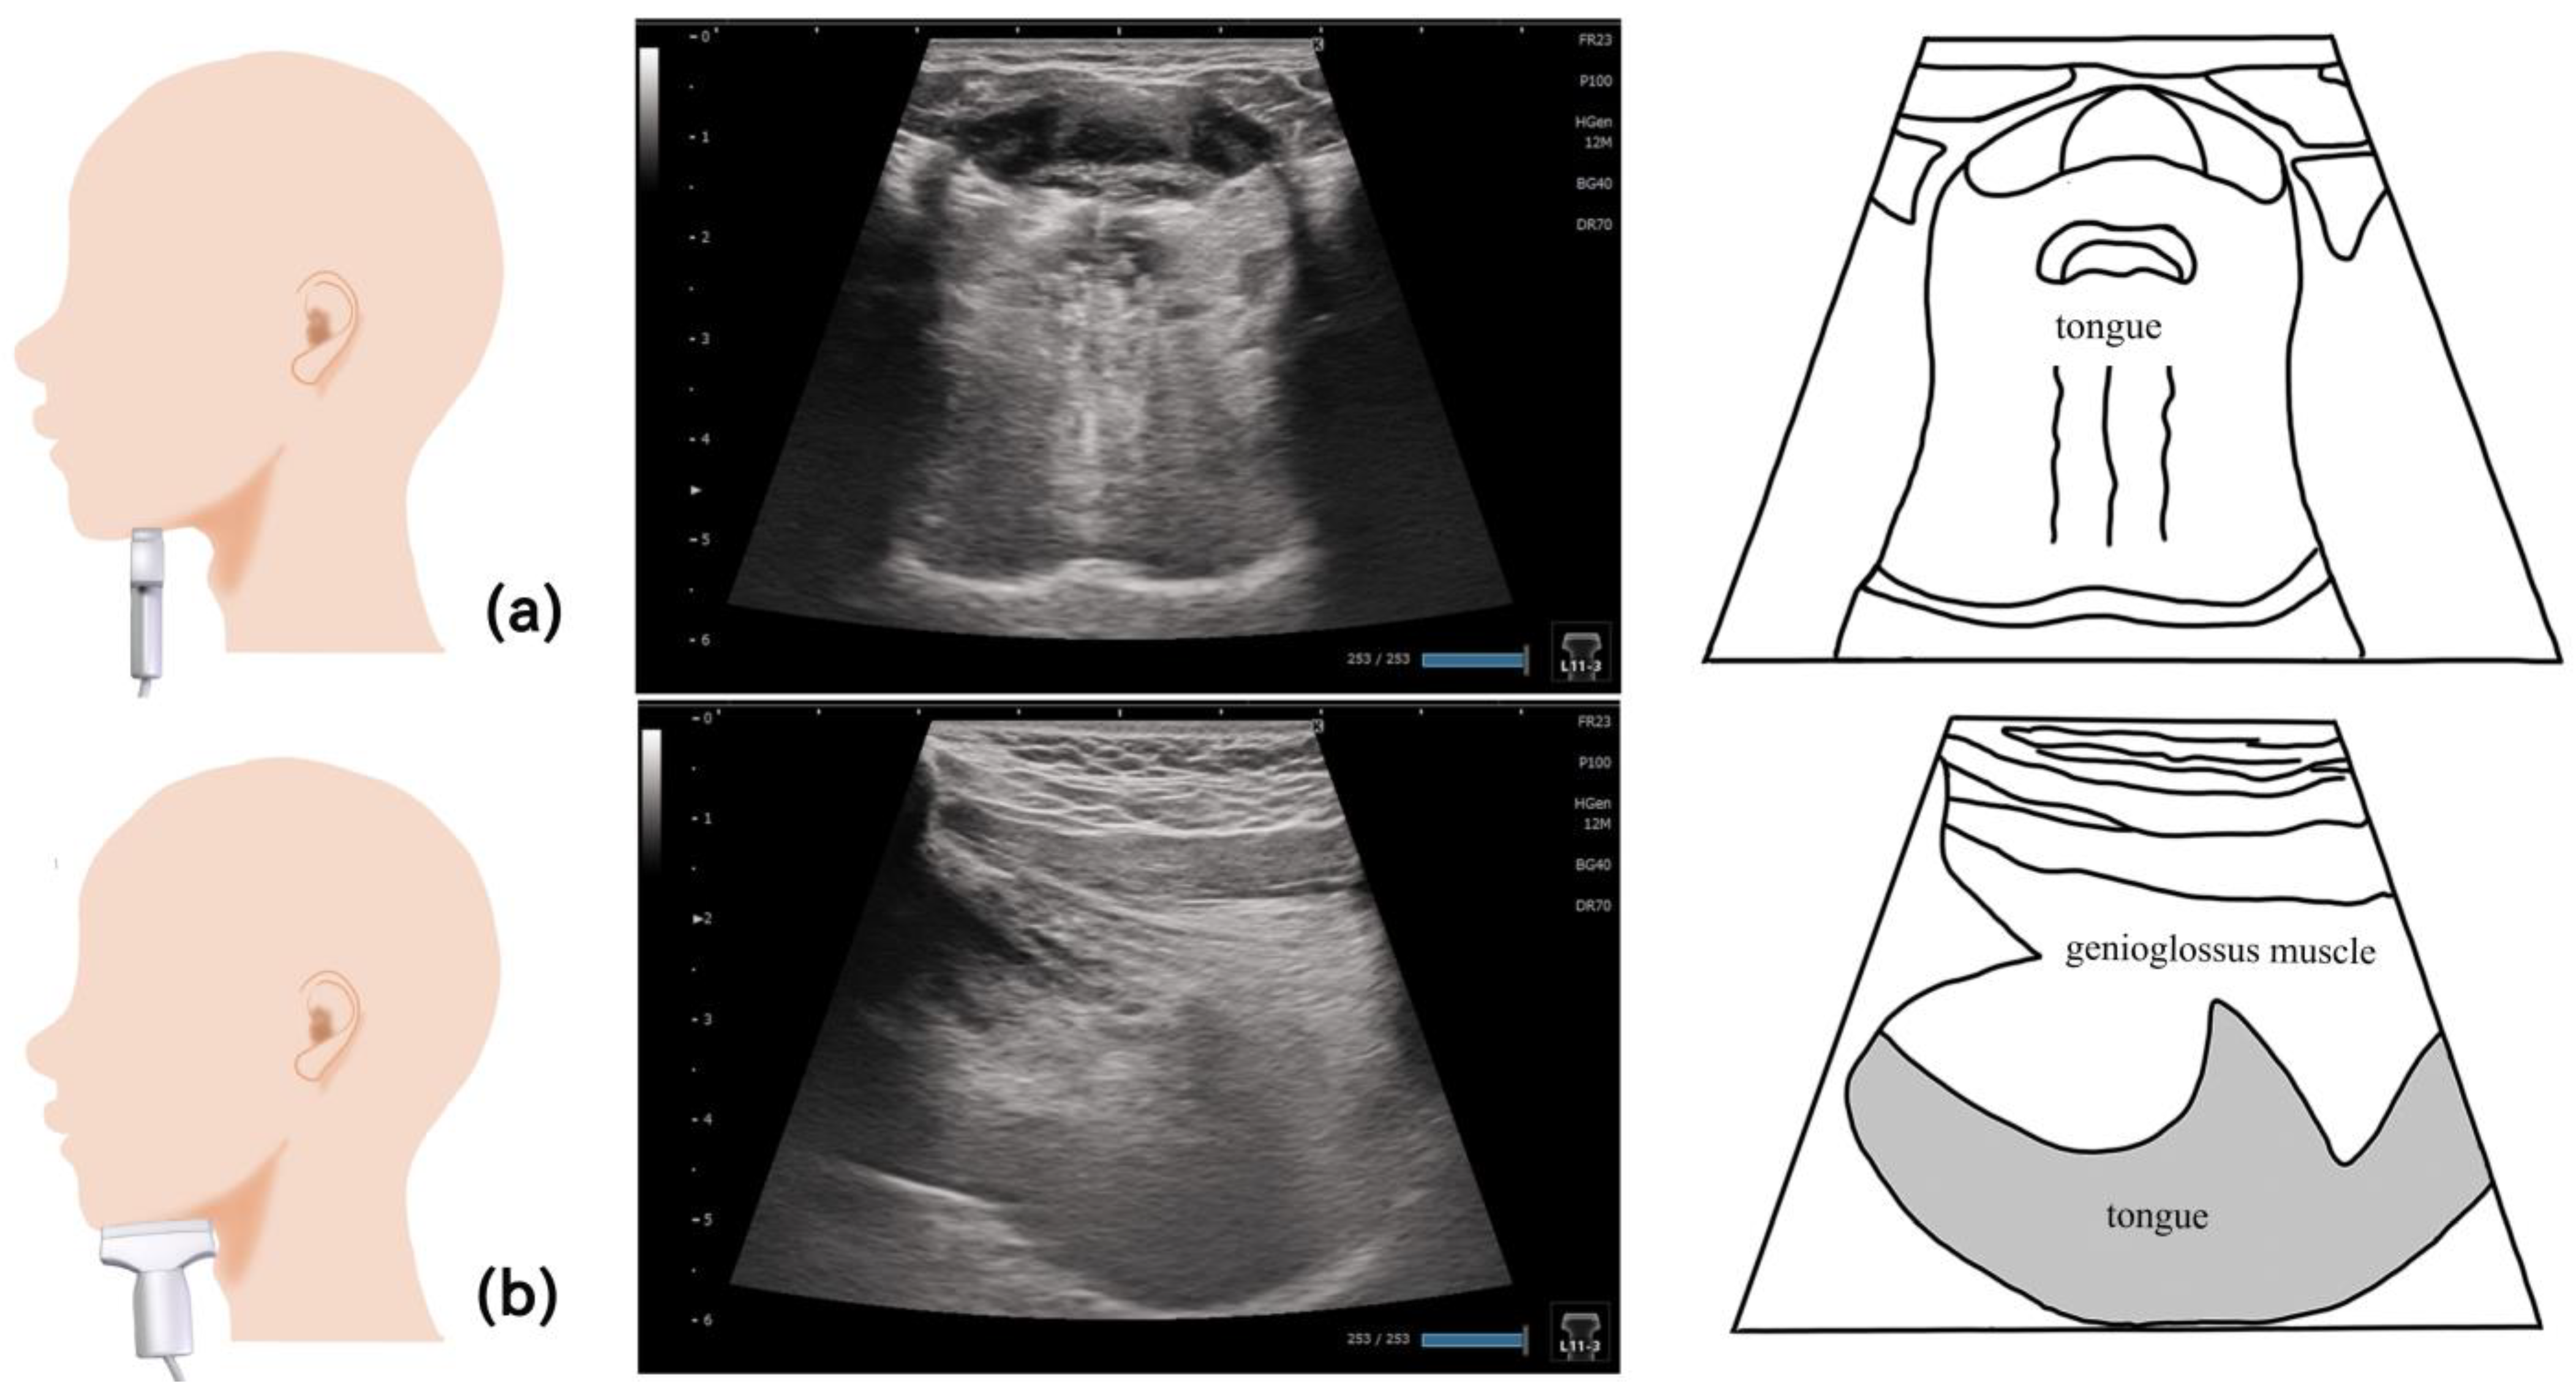

6. Tongue (Figure 4)

8. Genioglossus Muscle (Figure 7)